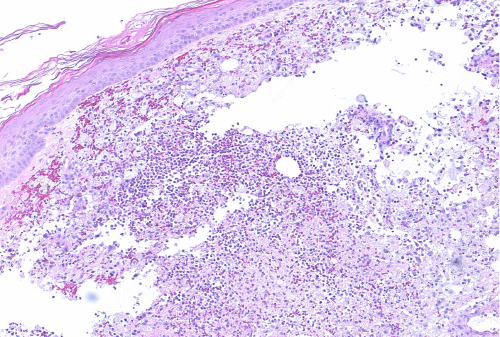

Upper endoscopy with endoscopic ultrasound was performed to evaluate for malignancy—no pancreatic mass was identified. Given the draining nodules on physical exam were suggestive of fat necrosis and an extensive rheumatologic workup of the patient's polyarthritis was negative, a skin biopsy of the left wrist nodule was performed. This demonstrated dense dermal and subcutaneous necrotizing neutrophilic inflammation consistent with pancreatic panniculitis (Figure 5).1 Wound culture from the nodules was negative for pathogenic organisms.

Figure 5. Representative Histopathological Images at (A) 20x, (B) 100x, and (C) 200x Magnification of Left Wrist Punch Biopsy. Published with Permission

Images demonstrate diffuse dermal and subcutaneous necrotizing neutrophilic inflammation.